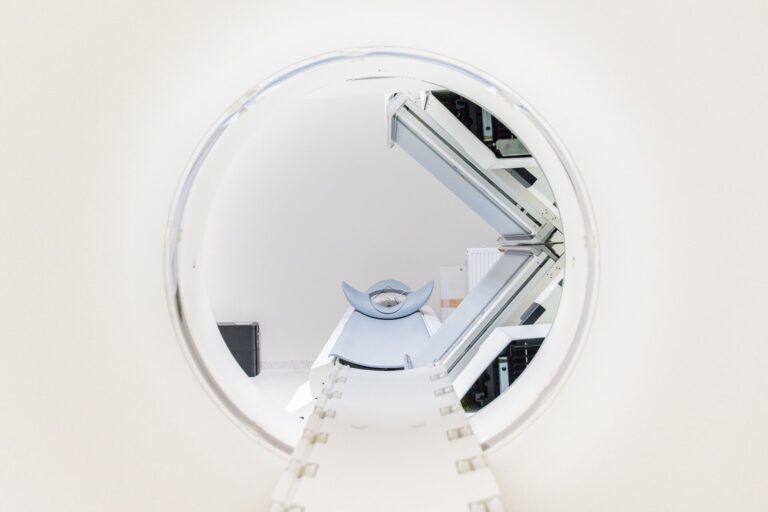

Complete-body MRI scanning has been accessible for a decade or extra. MRI makes use of robust magnetic fields to coax a sign from water molecules. Given our physique is roughly 60% water by quantity, MRI scans can be utilized to generate pictures over the size of our physique. In a scientific setting, scans are then studied by radiologists who search for potential abnormalities.

Latest technical enhancements imply detailed pictures of the physique from head to toe can now be obtained in lower than half an hour. This method has been primarily used for most cancers detection.